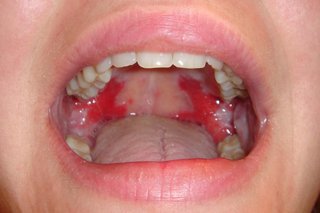

Pemphigus vulgaris inside a person’s mouth. There are red, sore-looking patches covering the roof of the mouth.

The most common area affected is inside the mouth and throat, which can make swallowing painful.